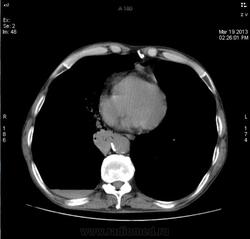

При поступлении одышка, кашель, Т до 37. "Рентгенкартина пневмонии справа, пневмосклероз, эмфизема. Киста, булла слева?" Прошу прощение за качество, снимки"с рук".

Выставлен центральный рак, буллезная болезнь.

На фоне эмфиземы и булл имеется размытая интенсивная инфильтрация в S8 справа и гидроторакс в наддиафрагмальной зоне. НО... Уровень-то горионтальный, значит есть сообщение с воздухом. Пути два: снаружи (пункция) и изнутри (прорыв буллы, абсцесса, кисты). На реформатах жидкости нет.

Абсолютно верно, все сказанное по снимкам. Так и было расписано. Но на КТ выявилось- жидкость кисте или полости не принадлежит, жидкость "за" буллой. Между стенкой буллы и плеврой! За качество еще раз прошу прощения( из рук вырывал! не дали снять нормально) Реформаты - те что были предоставлены на распечатке! Вот и реши... Пришлось пересматривать КТ самому .

Добавила аксиалы с видео в начале темы. По КТ: ну, буллы, ну, компрессия нижней доли и неполная - средней. Гидропневмоторакс справа. Эмфизема. Рака не увидела.

Ну, рака бы я конечно не поставил. КТ-признаки эмфиземы легких, буллезной эмфиземы, пневмогидроторакса в переднем отделе справа; сзади справа, считаю большая киста/кисты с уровнем жидкости.